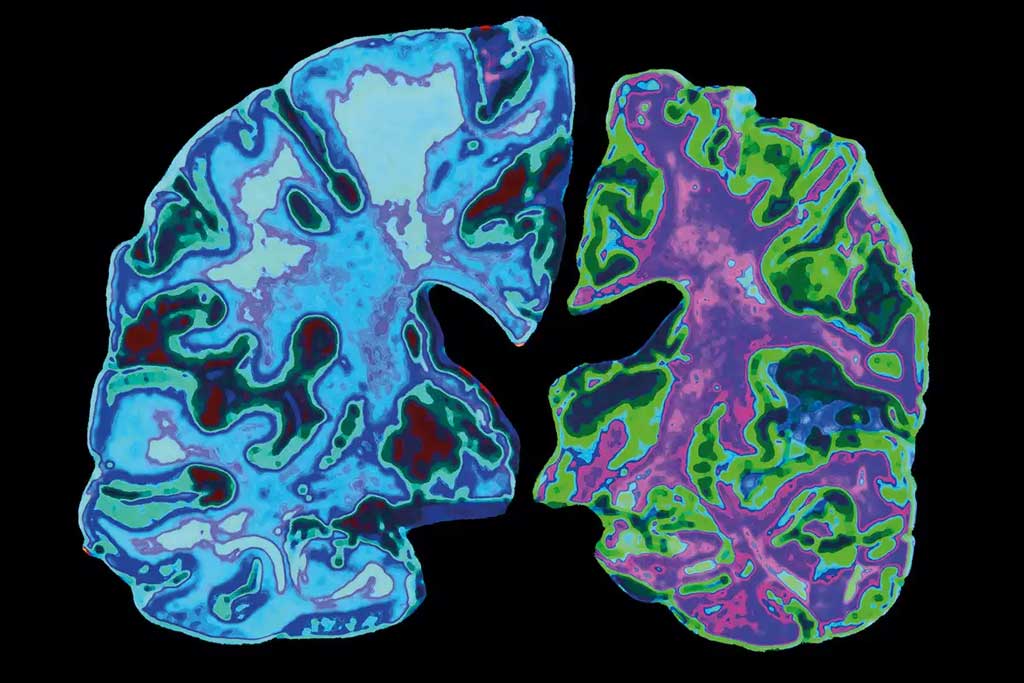

طبق مقاله منتشر شده در ژورنال علمی آلزایمر، جوان چینی مورد بحث از سن ۱۷ سالگی دچار افت عملکرد حافظه شده است و با گذشت چند سال، مشکلات مربوط به فراموشی وی رو به وخامت رفته است. تصویربرداری پزشکی صورت گرفته از مغز او نشان می‌دهد که ناحیه هیپوکامپ بیمار دچار تحلیل شده است. ناحیه گفته شده در مغز، نقش اساسی در عملکرد‌های مهم مثل یادگیری و حافظه را برعهده دارد. معمولاً آسیب به هیپوکامپ یا برداشتن آن با جراحی موجب اختلالات عصبی جدی می‌شود. همچنین در مایع مغزی – نخاعی او هم نشانگر‌های رایج آلزایمر تشخیص داده شده است.

شایان ذکر است که پژوهشگران دانشگاه پزشکی کپیتال در پکن موفق نشدند تا جهش‌های رایج شناخته شده برای از دست دادن حافظه را در ژنوم این بیمار ۱۹ ساله شناسایی کنند. حتی در تحقیقات گسترده‌تر، هیچ ژن مشکوکی در نمونه‌های بدست آمده از وی یافت نشد. تا پیش از این، جوان‌ترین فرد مبتلا به آلزایمر، بیماری ۲۱ ساله بود که ژن جهش یافته PSEN۱، زمینه را برای بروز بیماری او فراهم ساخته بود. افرادی که حامل این ژن باشند، دچار اختلال در ساخت پروتئین داخل مغز می‌شوند و پروتئین‌های معیوب می‌توانند پلاک‌های بیماری‌زا را در مغز تشکیل دهند.

تشخیص آلزایمر در جوانی ۱۹ ساله که هیچ سابقه خانوادگی از آلزایمر یا سایر بیماری‌ها و تروما نداشته است، امر بسیار عجیبی است و به دلیل عدم یافتن جهش در ژن‌ها، نمی‌توان او را در میان بیماران مبتلا به آلزایمر ارثی قرار داد. اما علائم بیماری او شباهت زیادی با آلزایمر دارد؛ به‌طوری که از دو سال قبل با از دست دادن تمرکز در کلاس درس شروع شده‌اند و اکنون به مرز اختلال در حافظه کوتاه مدت رسیده‌اند. امتیاز تست حافظه او، حدود ۸۰ درصد از هم‌سالان خود کمتر بوده؛ اما خوشبختانه همچنان می‌تواند به صورت مستقل امور فردی خود را اداره کند.